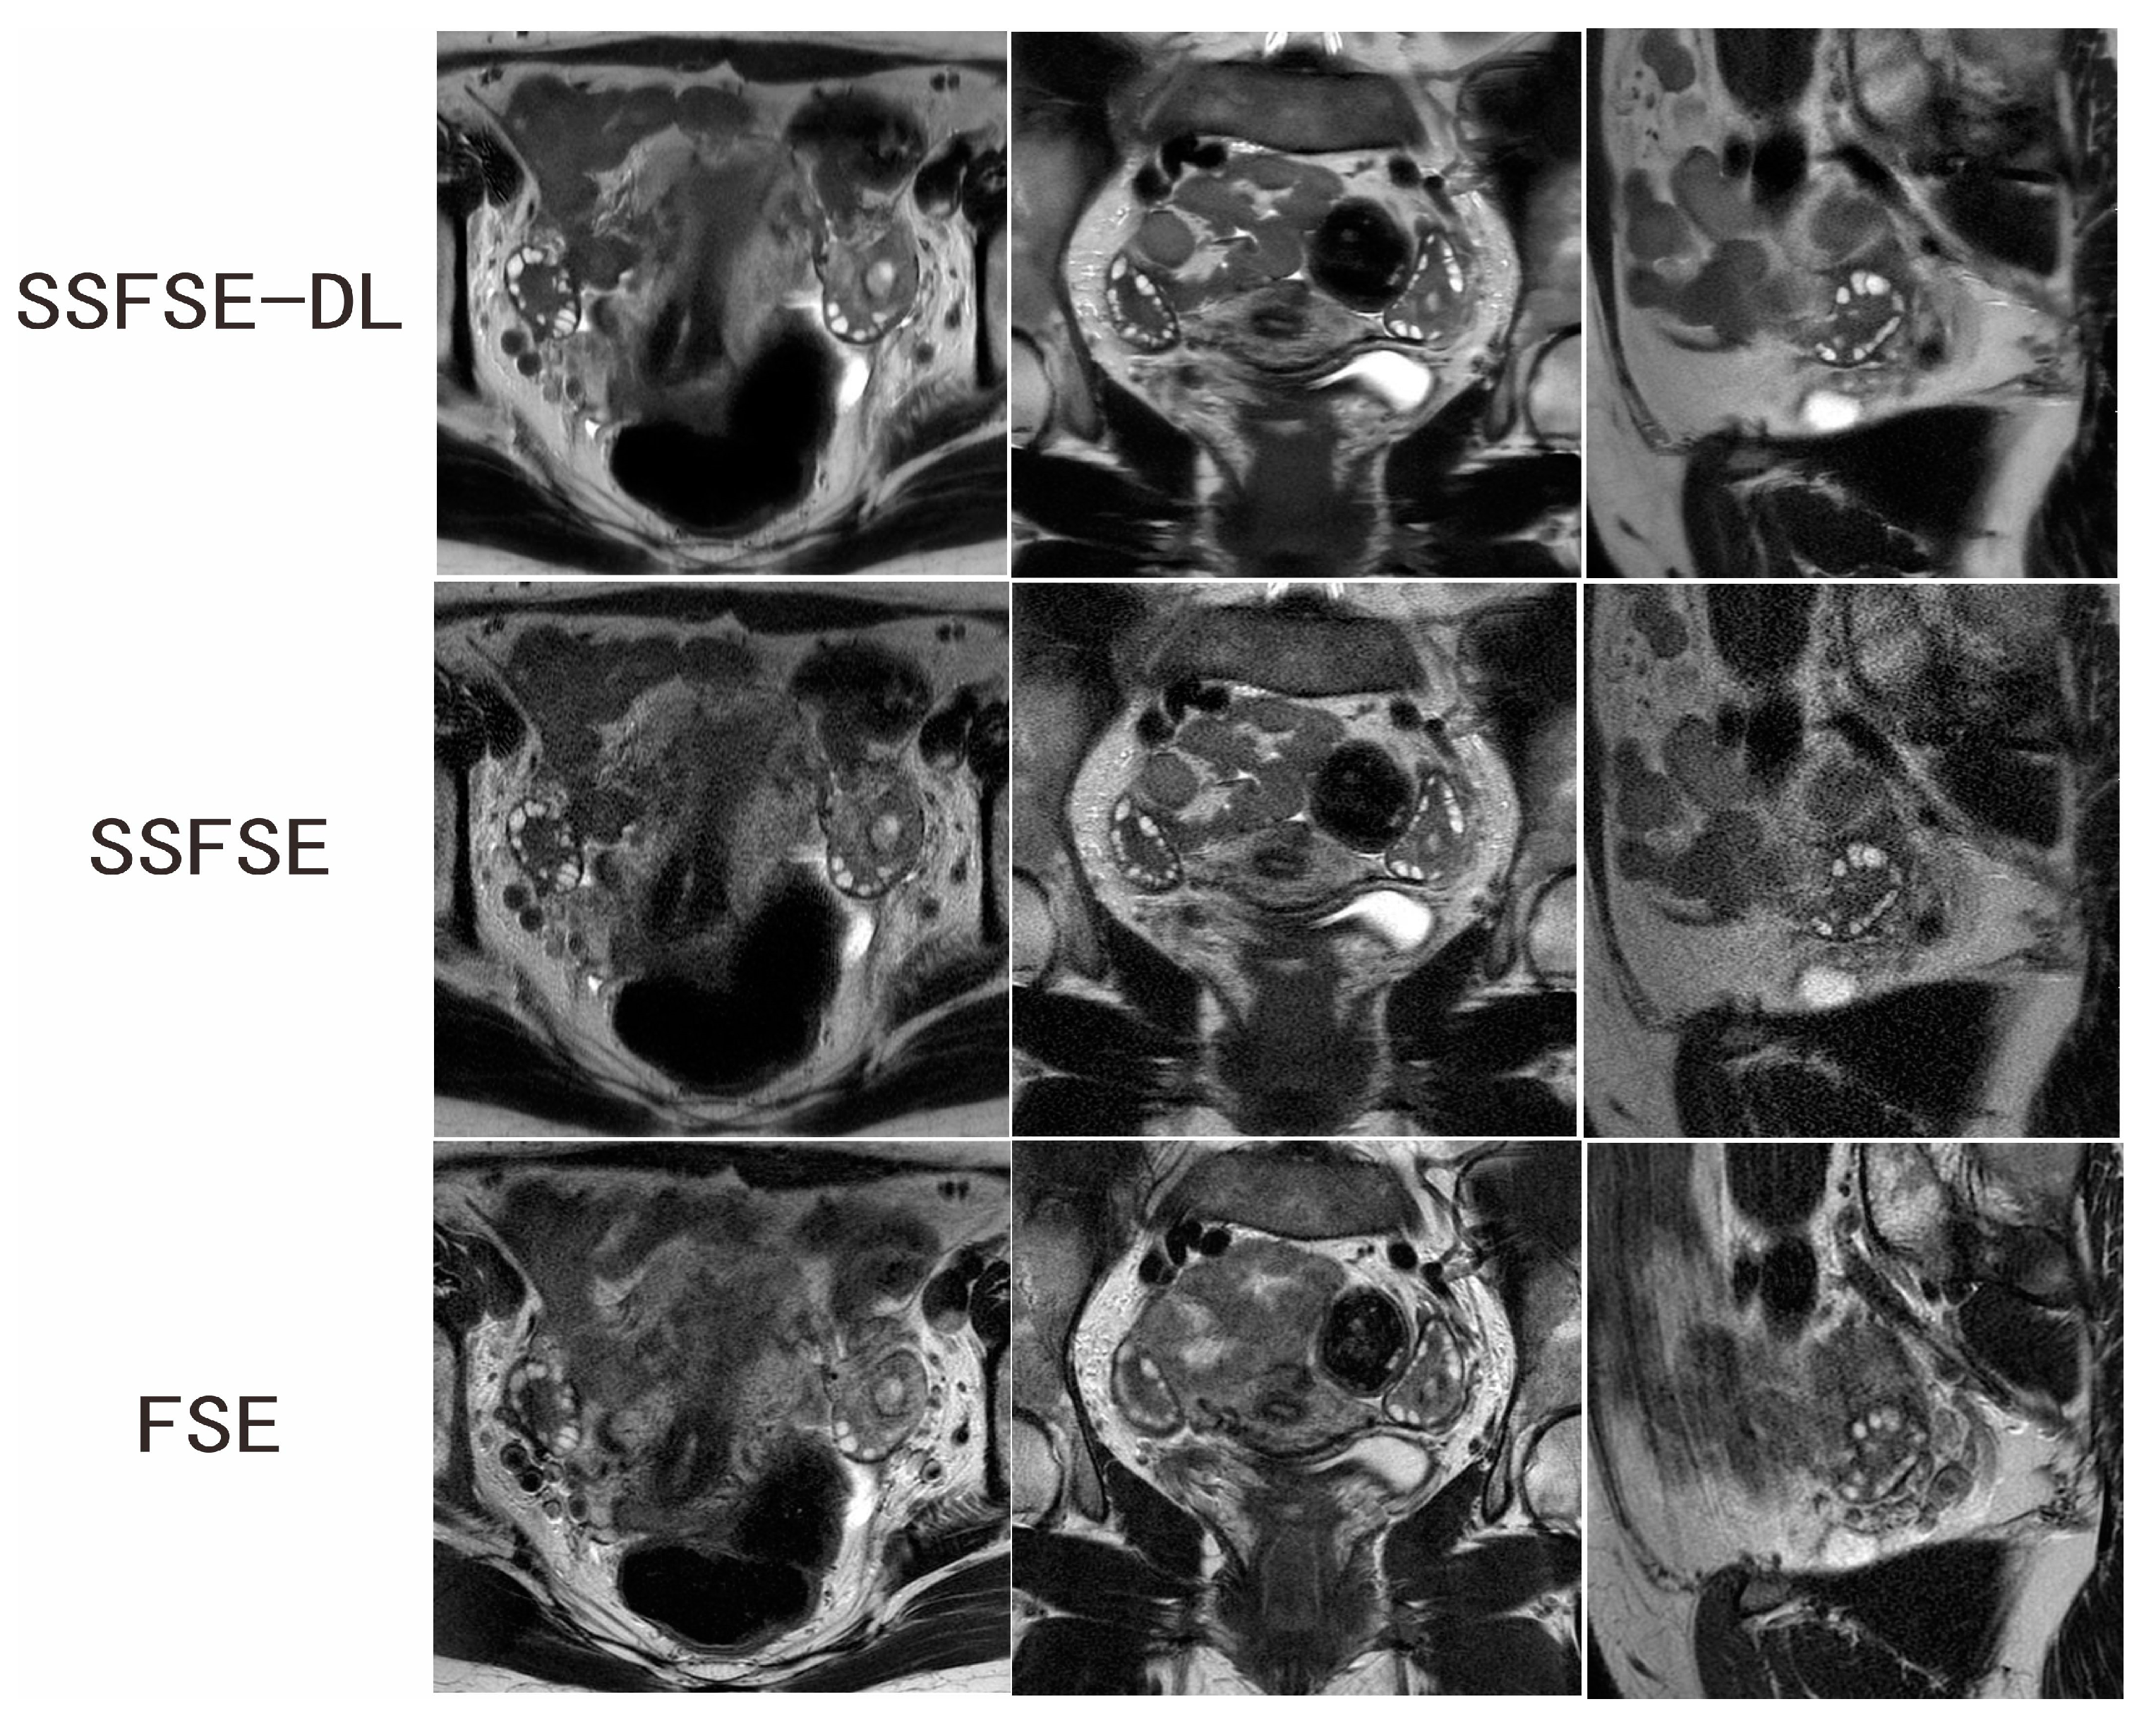

Figure 2.

Ovarian MRI in a 28-year-old woman with confirmed PCOS. SSFSE-DL images (upper row) show the least noise and blurring artifacts. The bilateral enlarged ovaries with many small peripheral follicles are clearly delineated on the SSFSE-DL images. The display of the follicles is impaired by the noise on the SSFSE images (middle row) and by the blurring artifacts in the FSE images (lower row).